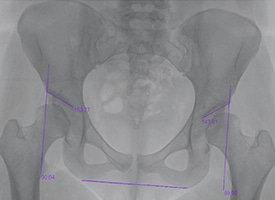

PRE OP

This x-ray demonstrates bilateral hip dysplasia with upward sloping hip sockets. This can cause early pain and degeneration of the hip joint.